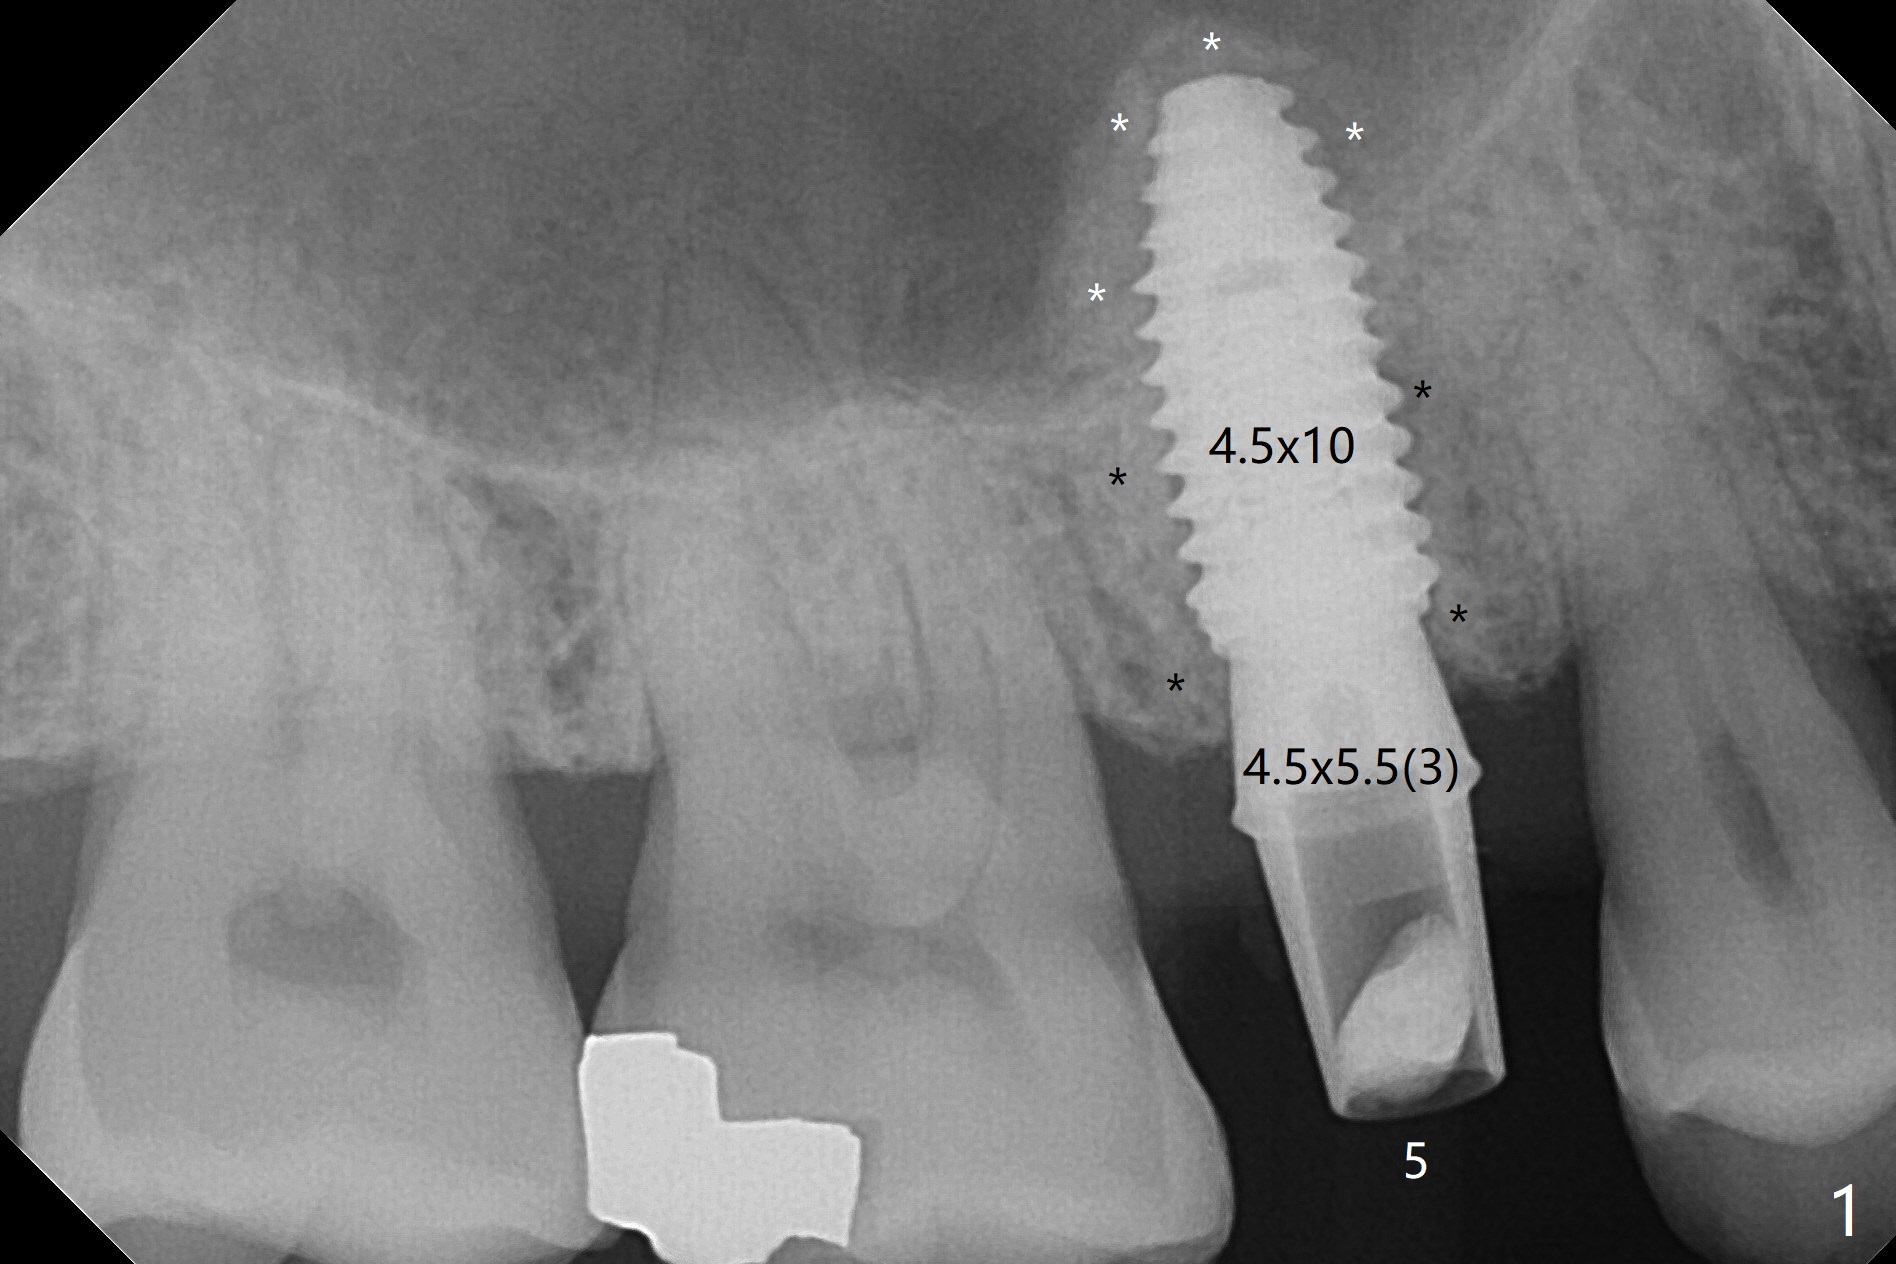

In fact the designed initial drills do not get to the bone with guides. After use of the next length drills (1.5 mm longer with sharp end), the sinus floor perforates without membrane perforation. Once 3.5 mm drill is used following sequential osteotomy, a 4x10 mm dummy implant is placed for sinus lift with 1 mm short of the depth and >50 Ncm. Following the dummy implant removal, allograft in the amount of 2 to 3 amalgam carriers is delivered for sinus lift (Fig.1,2 white *), followed by implant placement (4.5x10 mm, >55 Ncm). More allograft is placed before and after abutment insertion (black *). As usual, an immediate provisional is fabricated at each site. After removal and cleaning, the abutments are reseated and retorqued to 30 Ncm 11 months postop (Fig.3,4). Sinus lift is indistinct 15 months postop (Fig.5,6), probably due to radiation overexposure, although placement trajectory is good.